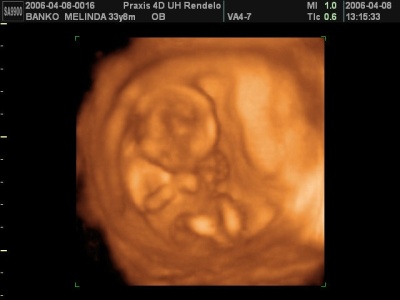

Kki, örülök, hogy jól sikerült a 4d-s uh-otok!